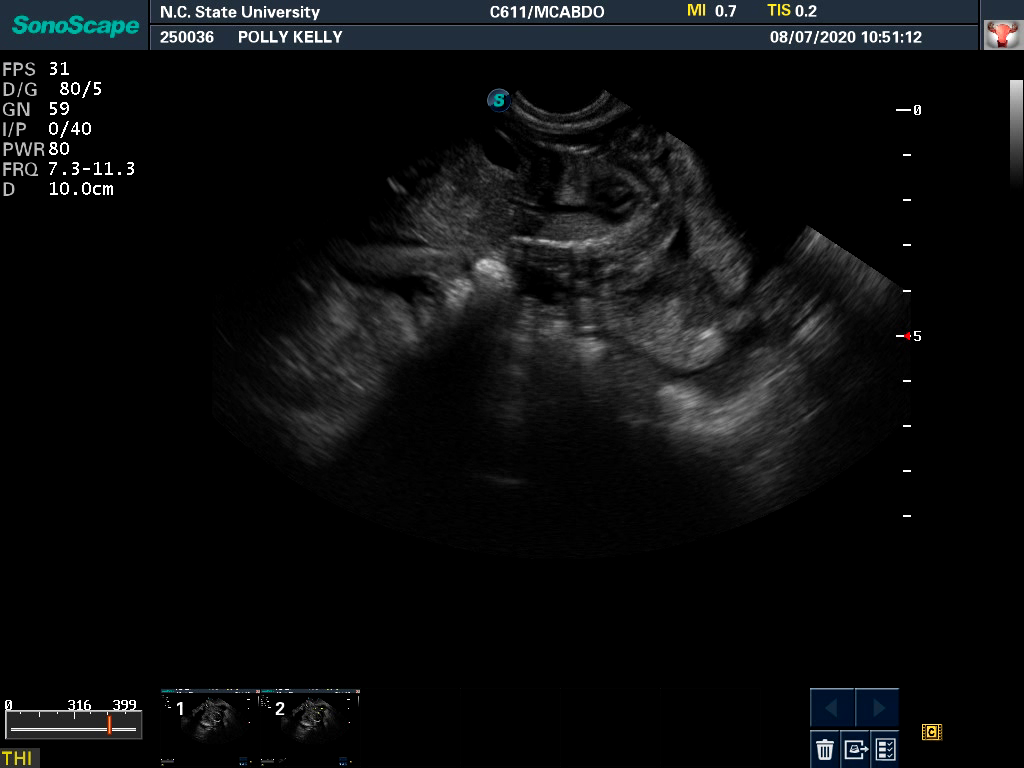

Polly had a "meet and greet" appointment with my repro vets at NC State University today. Polly had an ultrasound, and my vets said that they also think there are four puppies in there. (Although on the written discharge paperwork they said "three, possibly four" as ultrasound is an unreliable way to count puppies.) They said that all the puppies seem to be doing fine. Here is a picture from the ultrasound. In pre-pandemic days, I would have been in the room and the vets would have been pointing things out to me. Now of course, I have to wait in my car while they take Polly inside. I think that is a puppy at the top of the picture, with the head on the left and the spine being the bright line in the middle.